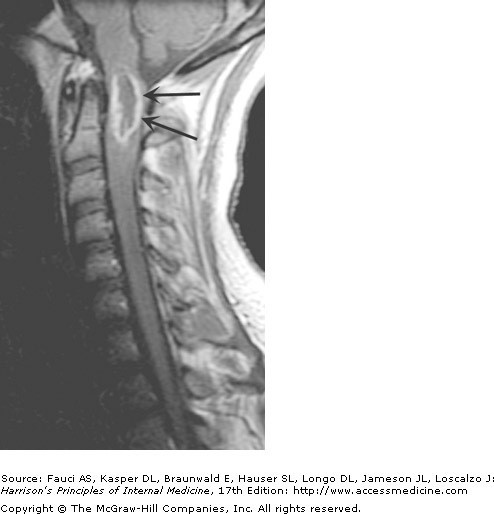

MRI: Intramedullary astrocytoma